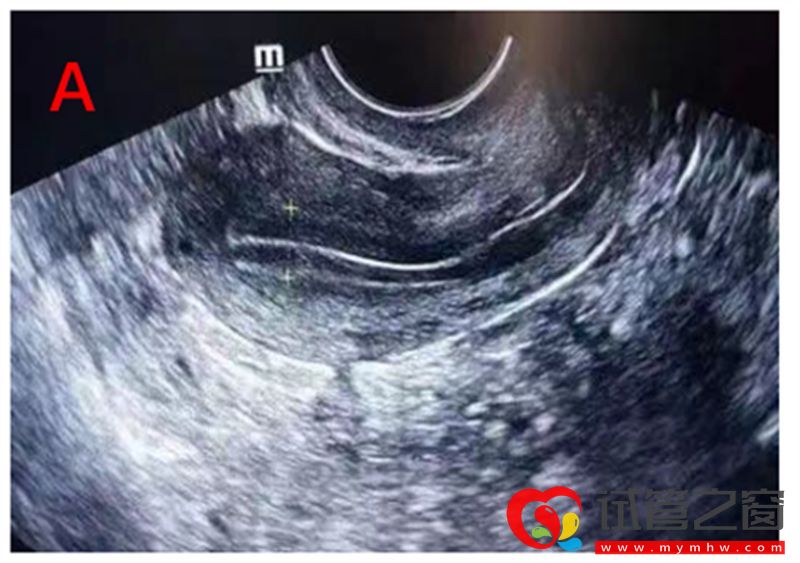

B超監測內膜

卵泡早期的內膜較薄,厚度約3~6 mm,隨著卵泡生長,雌激素水平逐漸升高,內膜不斷增厚。當卵泡達到成熟時,內膜厚度一般可達10-14mm。我們利用陰道超聲根據Gonen分型標準,對內膜形態進行分型,分為三型:A、B、C型。A型及B型子宮內膜的妊娠率顯著高于C型。

A型即三線型內膜,外層和中央為強回聲線,外層和宮腔中線間為低回聲區。常見于子宮內膜增生期。